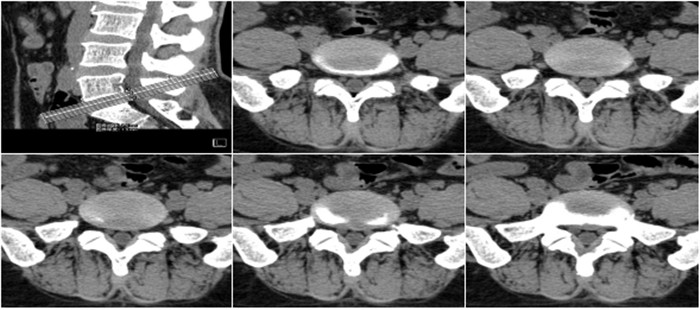

明峰CT搭載了領先的硬件技術平臺及系統,強大的掃描能力可滿足臨床的各種要求,呈現更極致的細節,為各臨床科室提供高品質的圖像。薄層掃描,消除部分容積效應,提高各向同性。配合高分辨率算法,有助于細微結構和形態學顯示。